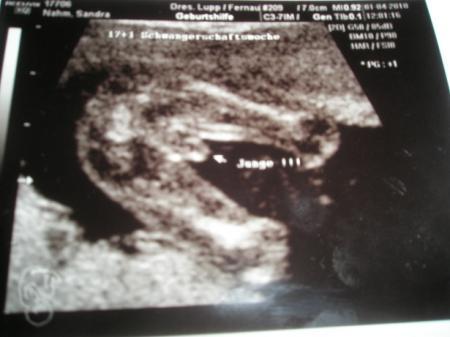

das sind ja echt süße Bilder, aber beim letzten kann ich auch nichts erkennen :-( naja bei sowas is es denk ich auch schwer. aber wen der Artzt das sagt meine ich auch das es so sein wirt schließlich werden die ja darfür ausgebildet :-) LG Sandra PS. das ist mein beweisbild das es ein junge wird :-)

Bild zu